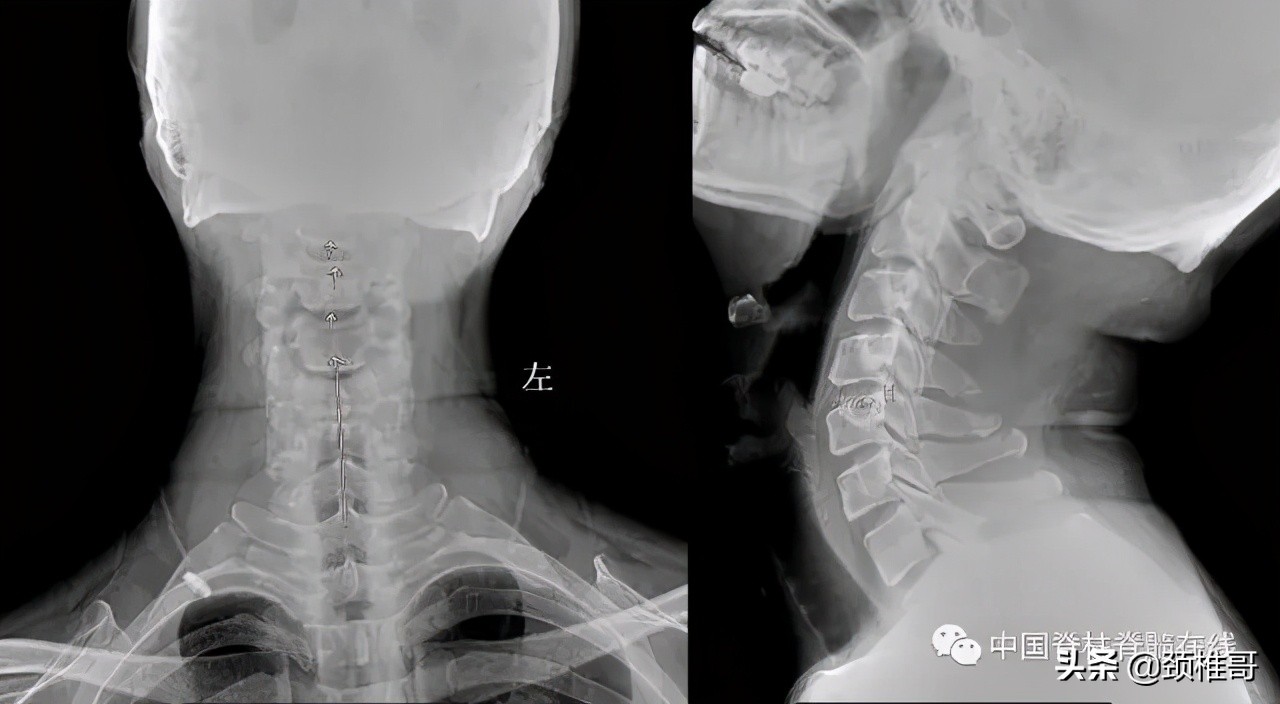

再看看这个病人,头晕2年,转头、低头时头晕加重,他的核磁共振显示椎间盘退变,水分减少了,但是没有明显的椎间盘突出,充其量算是膨出,但是我们看看他的x线片:颈椎3-5棘突序列不整齐,侧位显示颈椎5/6之间夹角增大,过伸位片显示,颈椎4-7各个节段夹角都超过了11°。过屈侧位片显示5、6、7三个节段出现了双边征,是椎体发生了旋转不稳的结果。这个病例的主要问题在于椎间盘吗?不对,在于肌肉和韧带针对颈椎4-7各个节段之间的稳定控制能力的减退。

正位:颈椎序列欠佳 侧位:颈椎4-7夹角增大

对节段颈椎成角过大、双边征

MRI显示颈椎多节段椎间盘退变膨出